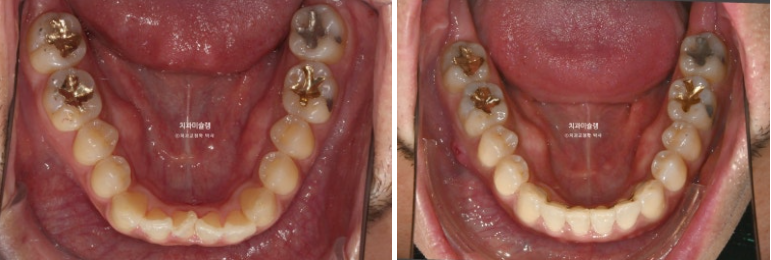

전 후 비교 보겠습니다.

24.07~25.10

중심선의 개선과 덧니의 해소

교정 후 치근흡수는 없고 뿌리 정렬상태도 좋습니다.